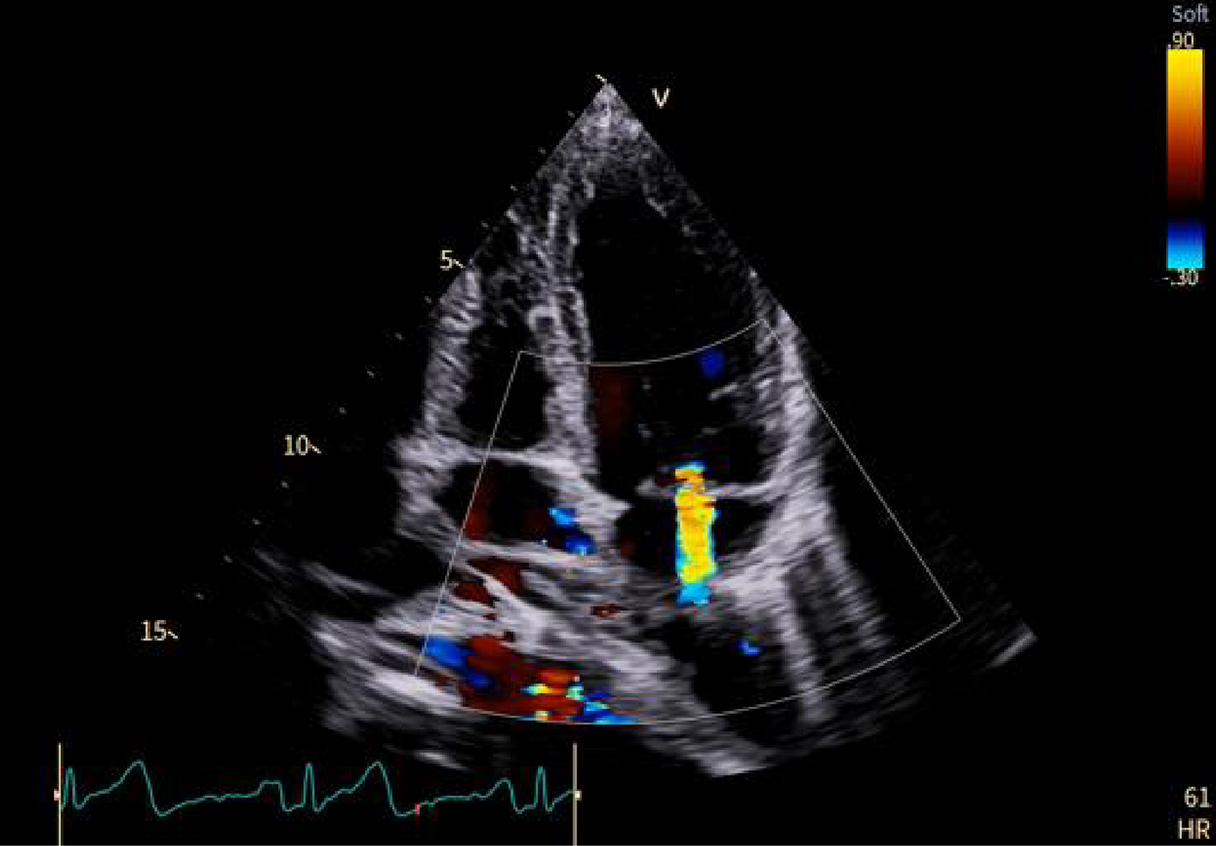

Casi clinici

Scopri come le tecnologie di imaging più innovative di GE HealthCare hanno giocato un ruolo chiave nella diagnosi di condizioni cardiache complesse.